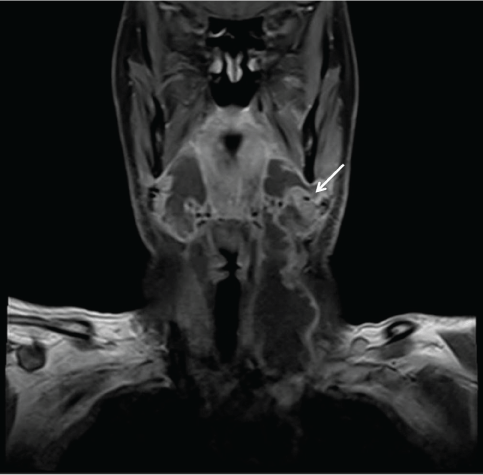

On USG; soft tissue thickening and tissue edema was seen in bilateral submandibular region, submental area and upper portion of the neck. Subsequently; CT was perfomed. CT revealed heterogeneous hypodense soft tissue thickening narrowing the air column in the left portion of the oropharynx at the level of the tongue base (Figure 1a). Left pyriform sinus is also seen as obstructed (Figure 1b). Neck MRI is performed with a clinical and radiological suspicion of LA and to be more confident about excluding a possible underlying malignancy. Neck MRI demonstrated subcutaneous soft tissue swelling and diffuse wall thickening of superior larynx, nasopharynx, oropharynx and hypopharynx (Figure 1). A cystic lesion with a 4.5 cm sized peripherally contrast enhancing was observed in the left peritonsillar area; diffusion restriction being demonstrated lesion was consistent with abcess (Figure 2 and Figure 3). In the submandibular and jugulodigastric areas, multiple LAPs were seen whose short axis was greater than 2 cm with a thickening cortex was observed. A significant clinical improvement was seen after iv amikacin and prednisolone initiation in patient who underwent surgical debridement. Cervical lymph node biopsies were reported as reactive hyperplasia on microscopic examination and surgically debrided tissue was pathologically confirmed as granulation tissue. Vancomycin and metronidazole were added to the antibiotherapy treatment and the patient was discharged with complete recovery.

Figure 3: On coronal plane; Diffuse soft tissue swelling and abcess in the left peritonsillar area is seen (arrow).